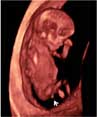

Esta ecografía en rotación muestra un embarazo gemelar de 12 semanas. La imagen en tres dimensiones muestra claramente dos fetos en sus respectivos sacos amnióticos. La membrana de separación entre ambas bolsas es bastante gruesa. Como la separación es muy clara, eso quiere decir que además de dos bolsas, existen dos placentas. Una de ellas se aprecia en la parte inferior izquierda de la cavidad uterina.

Ecografía 3D de gemelos de 12 semanas en bolsas diferentes